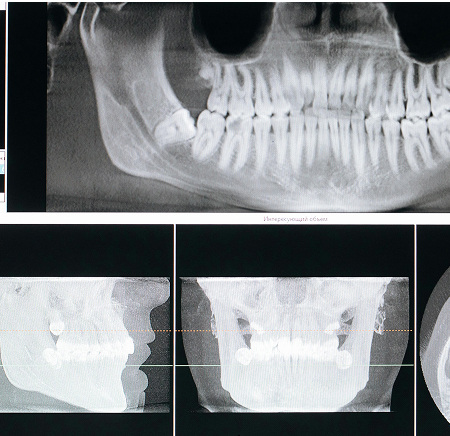

CBCTScan

A CBCT scan (Cone Beam Computed Tomography) is an advanced 3D imaging technique used in dentistry to capture highly detailed views of the teeth, jawbone, nerves, and surrounding structures. It provides precise, cross-sectional images, allowing dentists to diagnose and plan treatments with accuracy.

CBCT scan provides precise 3D imaging for dental implants, orthodontics, and oral surgery.